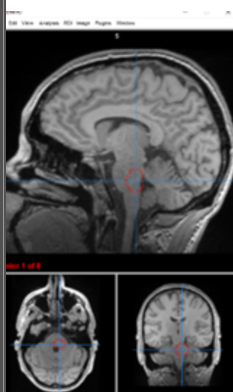

thalamus

filters information, regulates conscoiusness and sleep